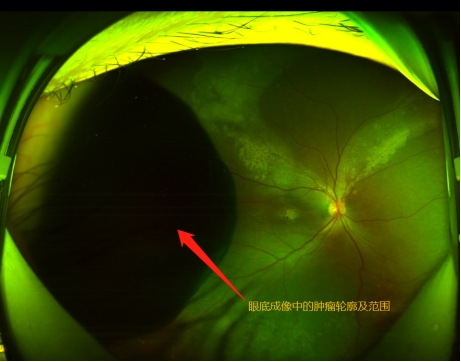

孙大卫在裂隙灯显微镜下发现晓琳的右眼内有一肿瘤,散瞳后肉眼可见瘤体。进一步检查发现,肿瘤位于患者右眼颞侧12点至6点钟位,纵径接近180度,从晶状体蔓延到眼底赤道部,横径超过15mm(而正常人的眼球直径约23mm),肿瘤在眼内脉络膜生长,瘤体向眼球内突出,高度约12mm。综合测量评估后专家认为肿瘤占据眼内体积的一半以上,且肿瘤生长速度较快,已经造成患者视物的遮挡,并逐渐出现肿瘤相关的眼内并发症,渗出性视网膜脱离,继发性白内障等,病情仍有进一步恶化的可能,建议手术治疗。

术前和术后的核磁影像学检查结果比较